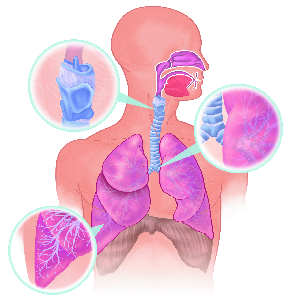

Über 860 Stichworte mit 120 Illustrationen auf 400 Seiten machen aus dem Lexikon der Lunge ein

wertvolles Werk.

Detailreiche Fotografien aus der medizinischen Praxis ergänzen die Texte; moderne, genaue,

wissenschaftliche Zeichnungen geben Einblick in die Anatomie und die Funktion der Lunge und

anderer Organe.